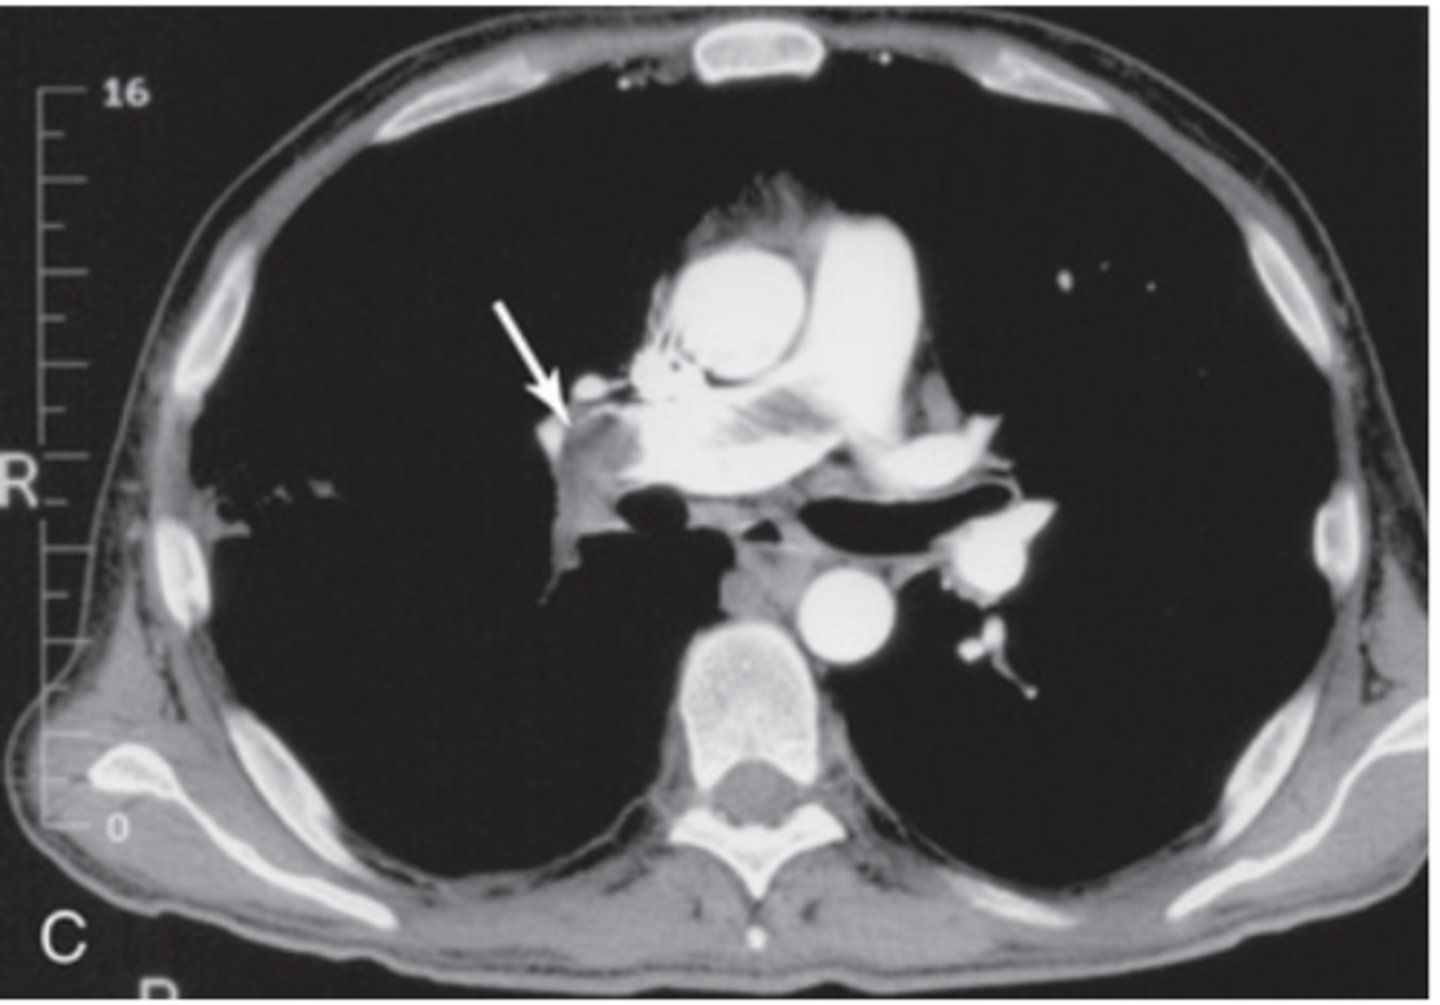

What does a Pericardial effusion look like on a chest CT?

Pericardial effusion

-waterbag appearence

-greater than 250mL to dtx on radigraph

-visible on CT, but procedure of choice is ECHOcardiography